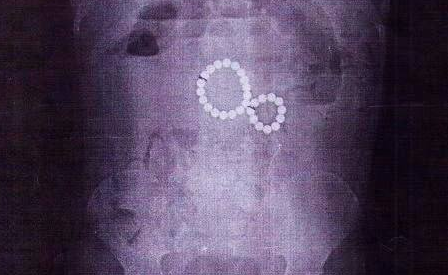

Ребенок поступил в местную больницу в очень тяжелом состоянии. У нее наблюдались разные признаки непроходимости кишечника, в том числе рвота с кровью. Врачи немедленно отправили девочку на рентген и увидели, что в ее кишечнике находится 29 магнитов.

Шарики притягивались друг к другу, что грозило разрывом кишки и летальным исходом, потребовалась экстренная операция. Хирурги прекрасно выполнили свою работу, аккуратно убрав все инородные предметы. Малышка уже идет на поправку.